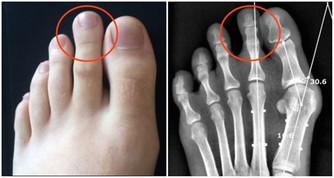

(1)有痛風病症的人群

五穀雜糧類食物,通常含有大量草酸,如果過量食用很有可能誘發痛風;

尤其豆類食物,少量食用就會導致尿酸增高,甚至還有可能誘發其他並發症。

因此,建議有痛風等病症的人群盡量少吃五穀雜糧類食物,以免導致痛風發作。